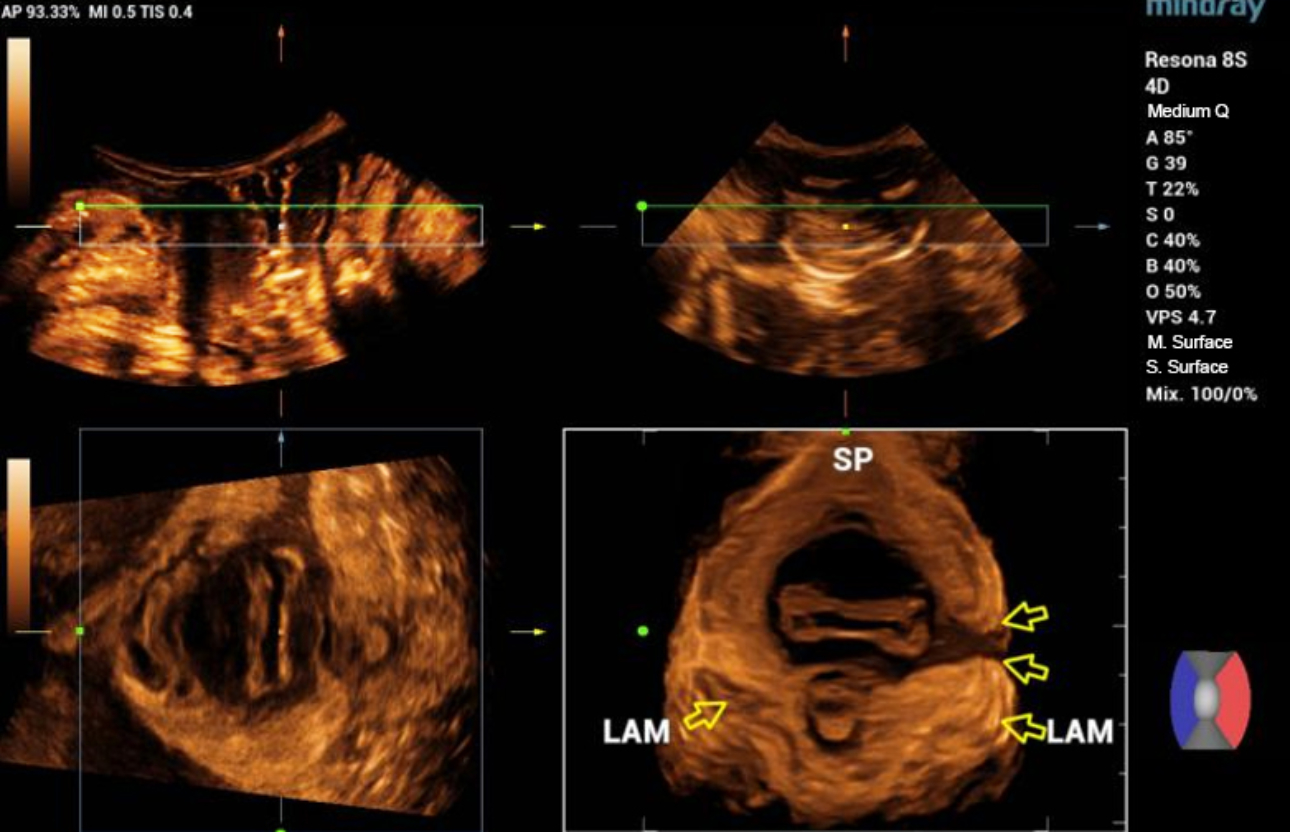

형상 3. 좌측 avulsion의 볼륨 이미징

levator-trauma-fig6-pc

형상 4. 좌측 avulsion의 Ipage+ 이미지